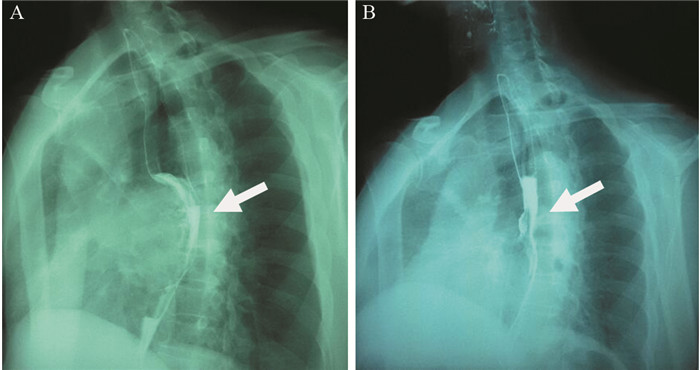

1 病例资料患者57岁,男性,因“进行性吞咽梗阻2月余,咳嗽伴痰中带血一周”于2015年7月16日入院。入院前2月余患者进食干硬食物时感吞咽梗阻。2月以来吞咽梗阻感进行性加重,并逐渐出现咳嗽、咯痰、痰中带血。胃镜提示:食管距门齿27 cm处可见巨大结节样新生物,见图 1A。纤支镜示:左主支气管上段内后壁外压隆起,未见新生物,见图 1B。病理学示:食管内恶性肿瘤倾向低分化癌,见图 2A。免疫组织化学染色:PCK(+)、CK7(+)、TTF-1(+)、CK5/6(-)、P63(-)、CD56(-)、Syn(-)、CgA(-)、NapsinA(-),支持低分化腺癌诊断,但不能确定为肺来源,见图 2A~2D。ALK经免疫组织化学ALK-V及FISH检测(ALK-FISH)均为阳性,见图 2E~2F。食管造影:食管中下段狭窄、管壁僵硬、黏膜破坏,病变长约10.5 cm,见图 3A。胸部增强CT见左肺下叶后基底段约3.7 cm×3.6 cm肿块影,呈分叶状,见毛刺征;纵隔及双肺门淋巴结肿大融合呈团块,最大者短径约3.0 cm;后纵隔约10.1 cm×5.8 cm肿块影,压迫食管,与食管壁分界欠清,见图 4A、4C、4E。头部MRI提示颅内转移瘤。上腹部CT、全身骨显像未见肿瘤转移征象。CEA 31.87 ng/ml,CYFRA21-1 15.49 ng/ml。颈部彩超提示右侧锁骨上区肿大淋巴结,较大约19 mm ×15 mm。入院前2月,体重减轻约20公斤。嗜烟30余年,每天10支。

| A: large esophagus mass with surface nodules (July 10, 2015); B: the uplift in the left main bronchus for external pressure (July 22, 2015) 图 1 纵隔及左肺恶性肿瘤伴食管癌待排患者胃镜及纤维支气管镜图像 Figure 1 Gastroscopy and fibro bronchoscope images of mediastinal and left lung malignancy coupling with suspicion for esophagus cancer patient |